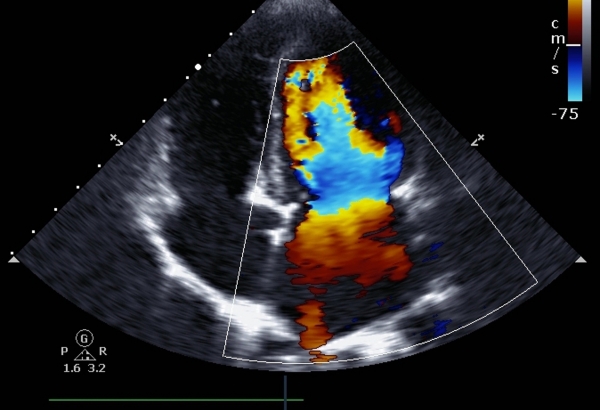

Flujometria Dopppler

Determinar la función placentaria, es decir, si los flujos de la placenta al útero son normales.

Verificar el estado de la circulación del feto con restricción en el crecimiento y se vigila el desarrollo de la circulación entre gemelos, asó como vigilar el riesgo de anemia secundaria en el feto por mamá RH negativo.

Es un complemento en el seguimiento del embarazo, en estos estudios valoramos el flujo sanguíneo del bebé, para determinar que los principales órganos fetales, tengan el flujo correcto de sangre para su función.